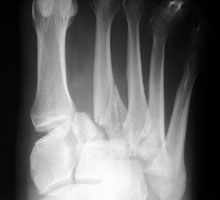

- Click on the image for a larger versionAAP radiograph of the forefoot. There is homolateral Lisfranc fracture-dislocation.